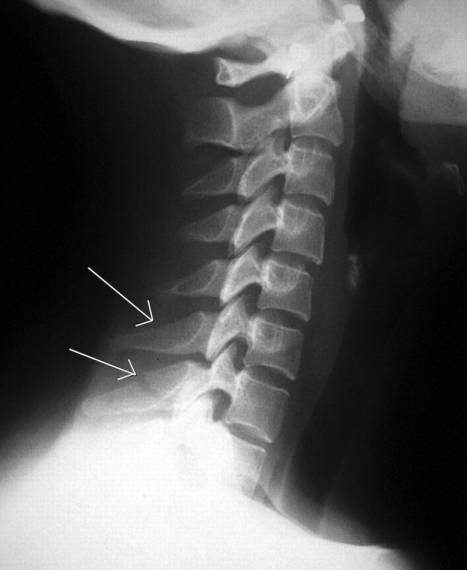

Clay shoveler骨折

下颈椎或上胸椎棘突骨折。1940年德国Hall等报道13例棘突骨折的患者,这些患者均为铲土工人,因此Hall将这类孤立性的棘突骨折命名为Clay shoveler骨折,即“铲土者骨折”。